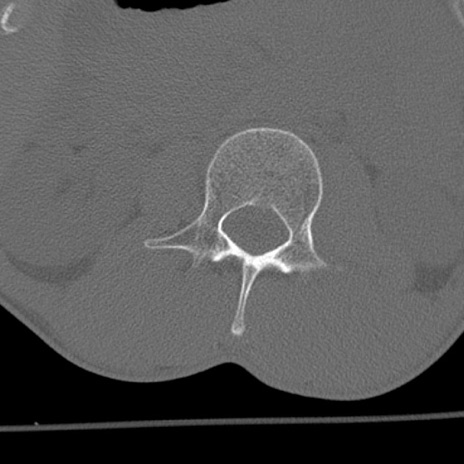

症例3 腰椎CT(横断像)

腰椎CT